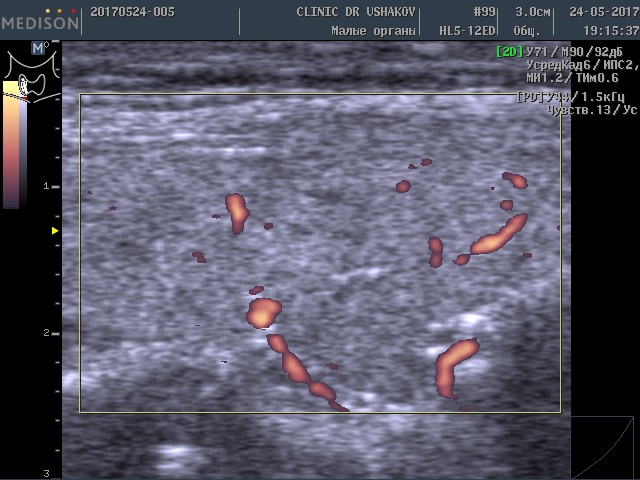

2) что усиленный кровоток в щитовидной железе (при УЗИ) ― признак перенапряжения и интенсивного образования гормонов тканью железы.

Обратите внимание на активность кровотока по данным УЗИ у этой пациентки (рис. 3 и 4).

Рисунки 3 и 4. Пациентка А., 26 лет левая и правая доли щитовидной железы в режиме ЭДК. Кровоток в малой и умеренной степени усилен (обозначен красным цветом).